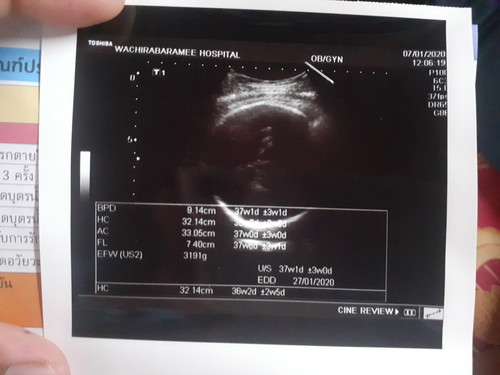

37+1w น้องหนัก 3,191g บ้านอื่นหนักเท่าไรกันบ้างเเล้วจร้าา